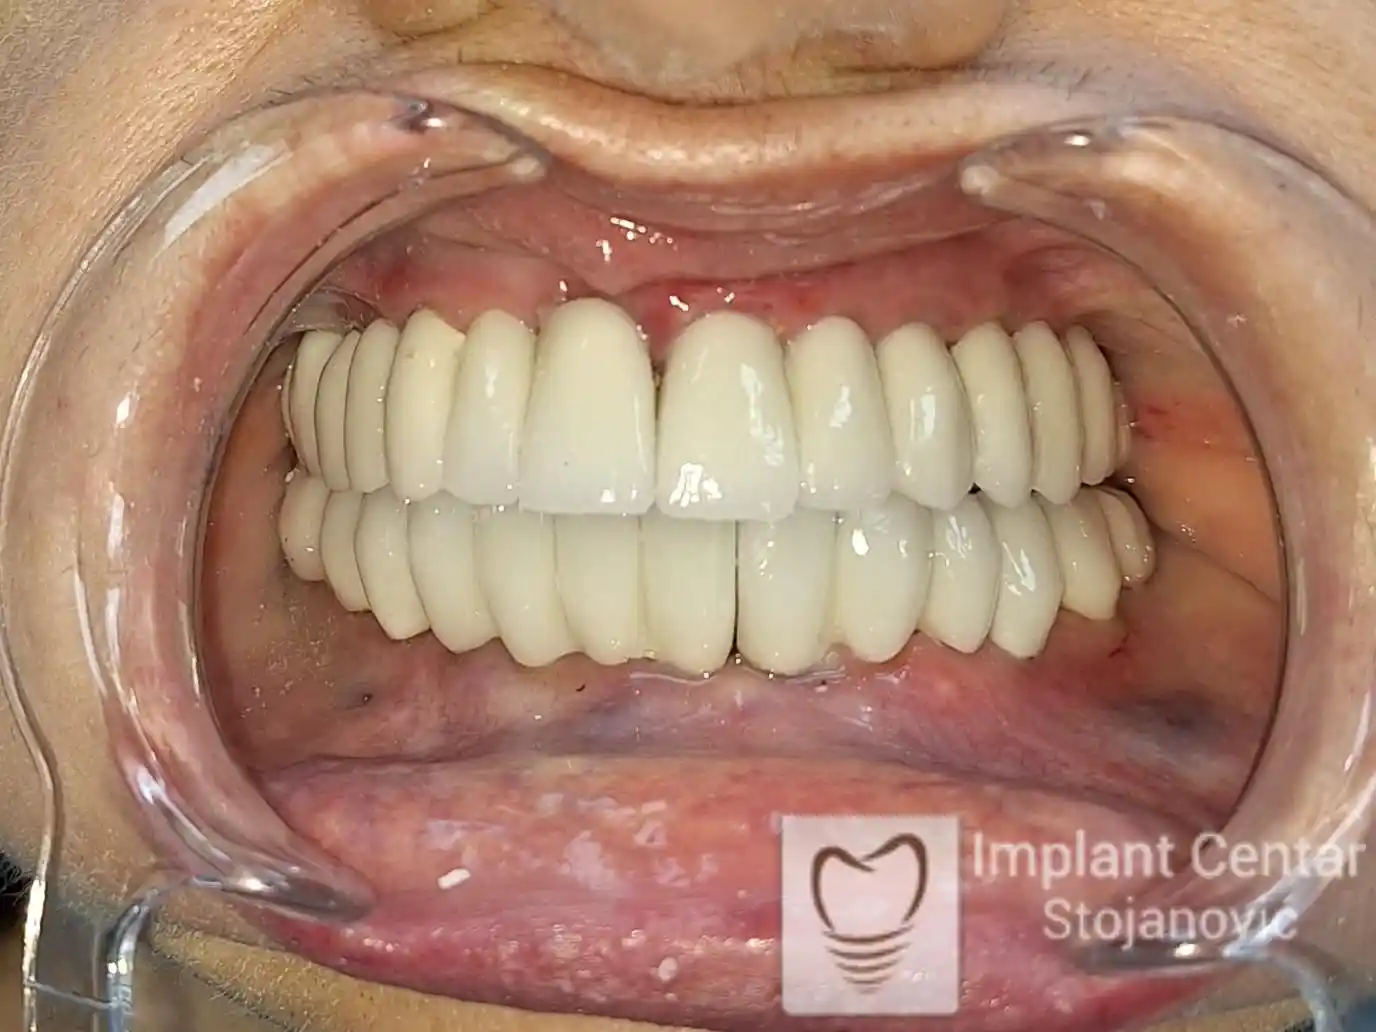

Već tri dana nakon operacije, pacijent je zbrinut fiksnim privremenim zubima na implantatima, čime je odmah povraćena funkcija i estetika osmeha.

Nakon završetka perioda integracije implantata, izrađeni su cirkonijum-keramički mostovi u gornjoj i donjoj vilici (slika 6.).

Pacijent ističe da je prezadovoljan rezultatom — po prvi put nakon dugo vremena može normalno da žvaće i grize hranu, uz prirodan izgled novog osmeha.